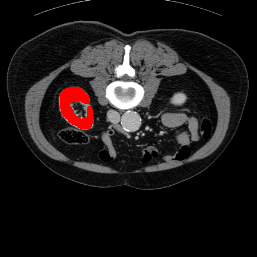

Support

Label

Proposed

In order to assess the performance of the proposed method, we compare the performance of the proposed model with excellent models in recent years. Table 1 and Table 2 shows the comparison results of different models in setting1, while Table 3 and Table 4 shows the comparison results of different models in setting2 on the data set in recent years. PANet[25] is the most widely influential few-shot model in the field of few-shot image segmentation on natural images. SENet [18] is the first few-shot segmentation model proposed for medical images. SSL-ALPNet[19] introduced the milestone of using superpixel self-supervision to train few-shot medical image models. RPNet[29] is a supervised method with a recursive mask optimization module to iteratively optimize the segmentation mask, [27] adapt it into the same self-supervision learning framework and applies setting1 to it and denoted as SSL-RPNet; CRAPNet[27] is the latest SOTA model for 2023. Compared with CRAPNet, our method outperforms most of the state-of-the-art models and only slightly outperforms CRAPNet. Figures 3 and 4 show examples of the model’s segmentation predictions on different datasets, respectively; The first row is the support map, the second row is the label map, and the third row is the segmentation prediction of the model.